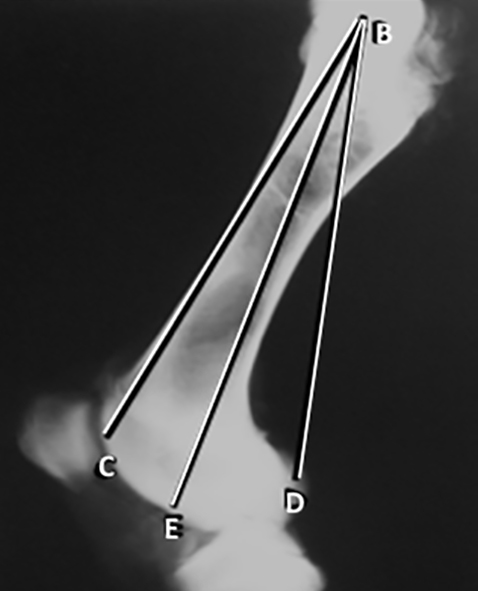

En las radiografías laterales del fémur, se trazaron y midieron otras 6 líneas (Figura 3) (Figura 4): 1. A-C: desde la punta del trocánter a la región más superior del cóndilo. 2. A-E: desde la punta del trocánter a la región medial del cóndilo. 3. A-D: desde la punta del trocánter a la región más inferior del cóndilo. 4.            B-C: desde el centro de la cabeza a la región más superior del cóndilo. 5. B-E: desde el centro de la cabeza a la región media del cóndilo. 6. B-D: desde el centro de la cabeza a la región más inferior del cóndilo.

Figura 3; Radiografía de perfil de fémur. Líneas desde la punta del trocánter mayor. A-C: a la región más superior del cóndilo. A-E: a la región medial del cóndilo. A-D: a la región más

Figura 4: Radiografía de perfil de fémur. Líneas desde el centro de la cabeza. B-C: a la región más superior del cóndilo. B-E: a la región media del cóndilo. B-D: a la región más inferior del cóndilo